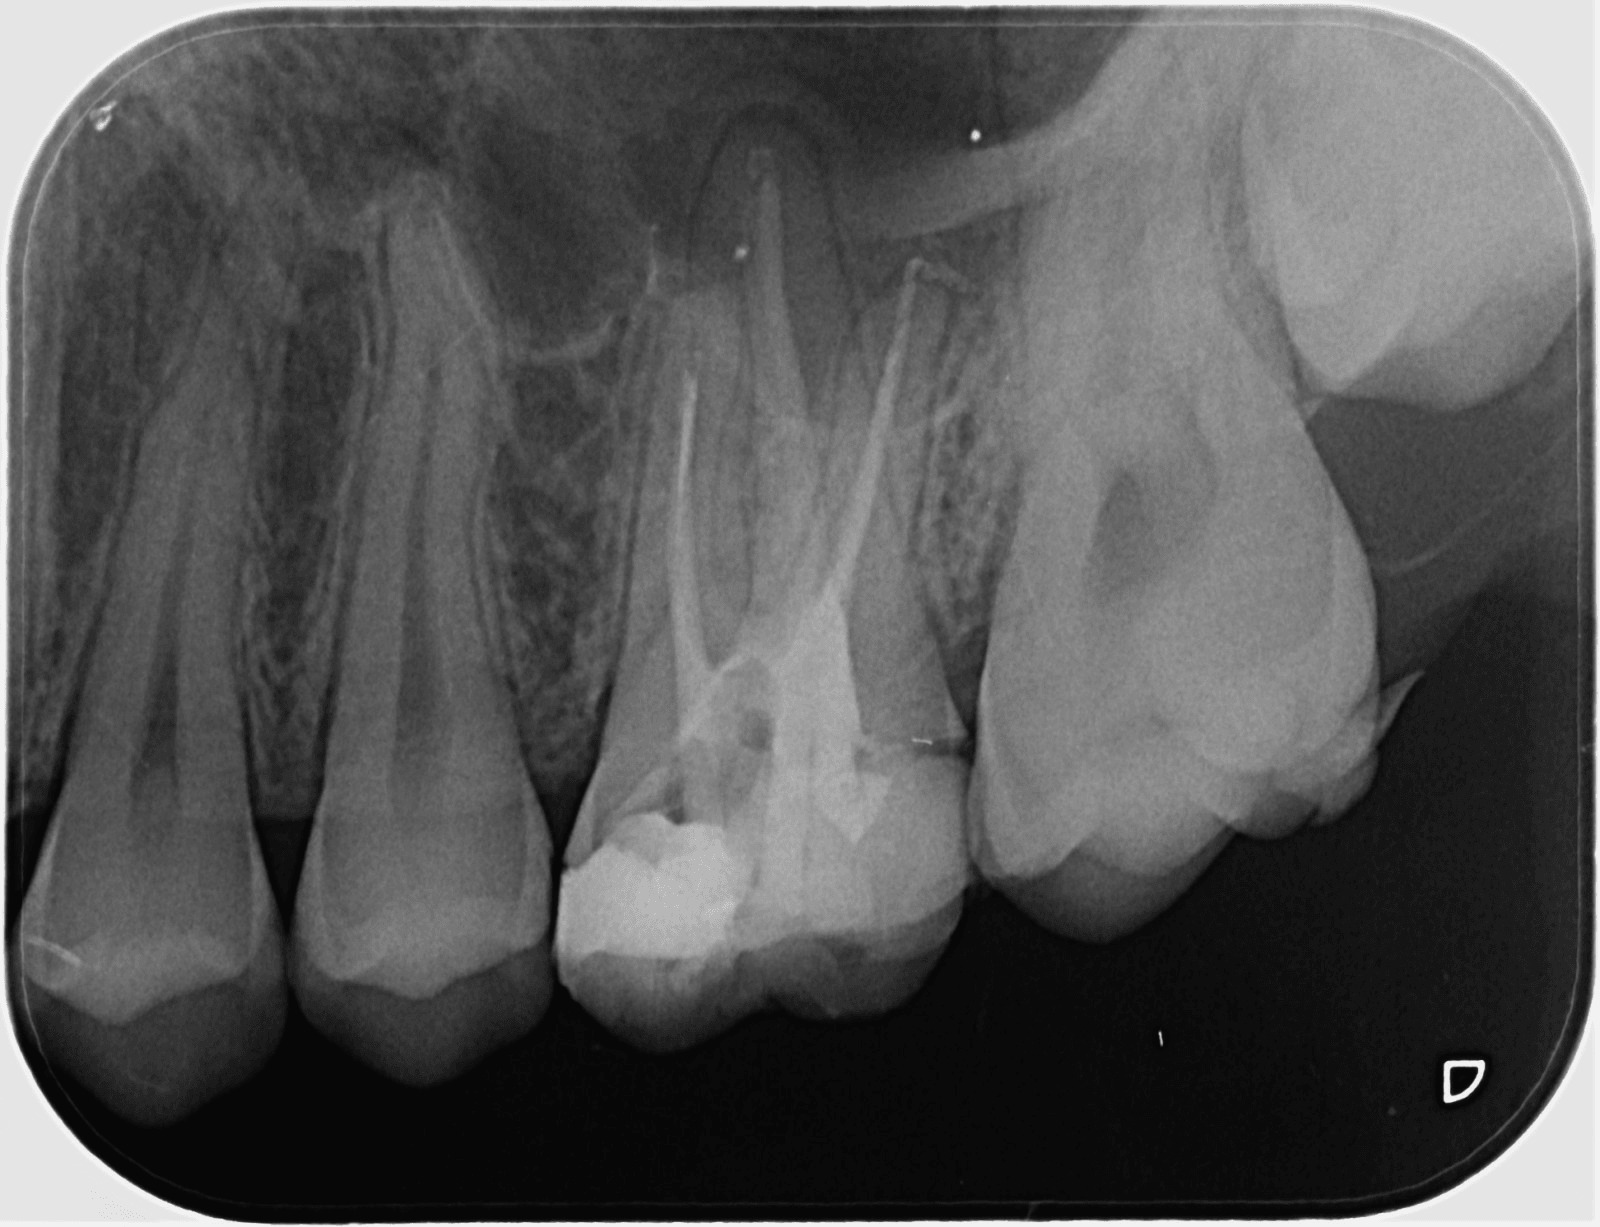

Секторни зъбни снимки

Това са най-разпространените зъбни снимки. За да имат добра диагностична стойност, те трябва да обхващат целия зъб - коронката, корена и прилежащата около него кост. Така лекарите по дентална медицина могат да констатират наличието на много заболявания като кариеси, грануломи, кисти, пародонтални проблеми, както и да проследяват развитието на кореново лечение или интеграцията на поставените импланти.